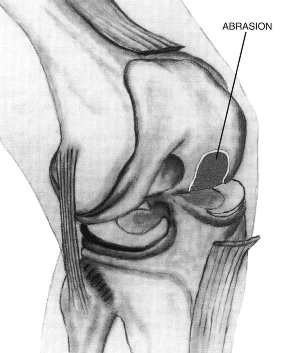

The aim of arthroscopic treatment of osteoarthritis and the osteotomy is to prevent the onset of the unwanted artificial joint by preserving the own knee or postpone it at least as much as possible.<br></br>Natural reparation processes can be stimulated by the so-called abrasion. The abrasion is a milling up of exposed cartilage-free bone (lunar landscape).<br></br>Only the top dead border lamella (about 2 mm) is milled to uncover blood vessels. The stability and carrying capacity of the joint are not reduced thereby. By exposing the blood vessels, the growth of a replacement cartilage is stimulated.

The dead and exposed bone layer is removed by abrasion to stimulate the body's own recovery processes.